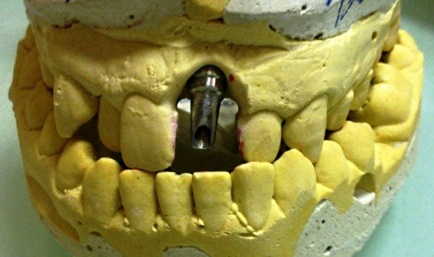

The surgery of an implant opening without a vestibule-oral graft throwing away was carried out in six months after the surgical stage. Availability of a sufficient amount of soft tissues in the region of implant placement made it possible to give up the usage of zirconium abutments and make use of a standard anatomic abutment to obtain positive clinical result.

The permanent metal-ceramic crown was manufactured later on.